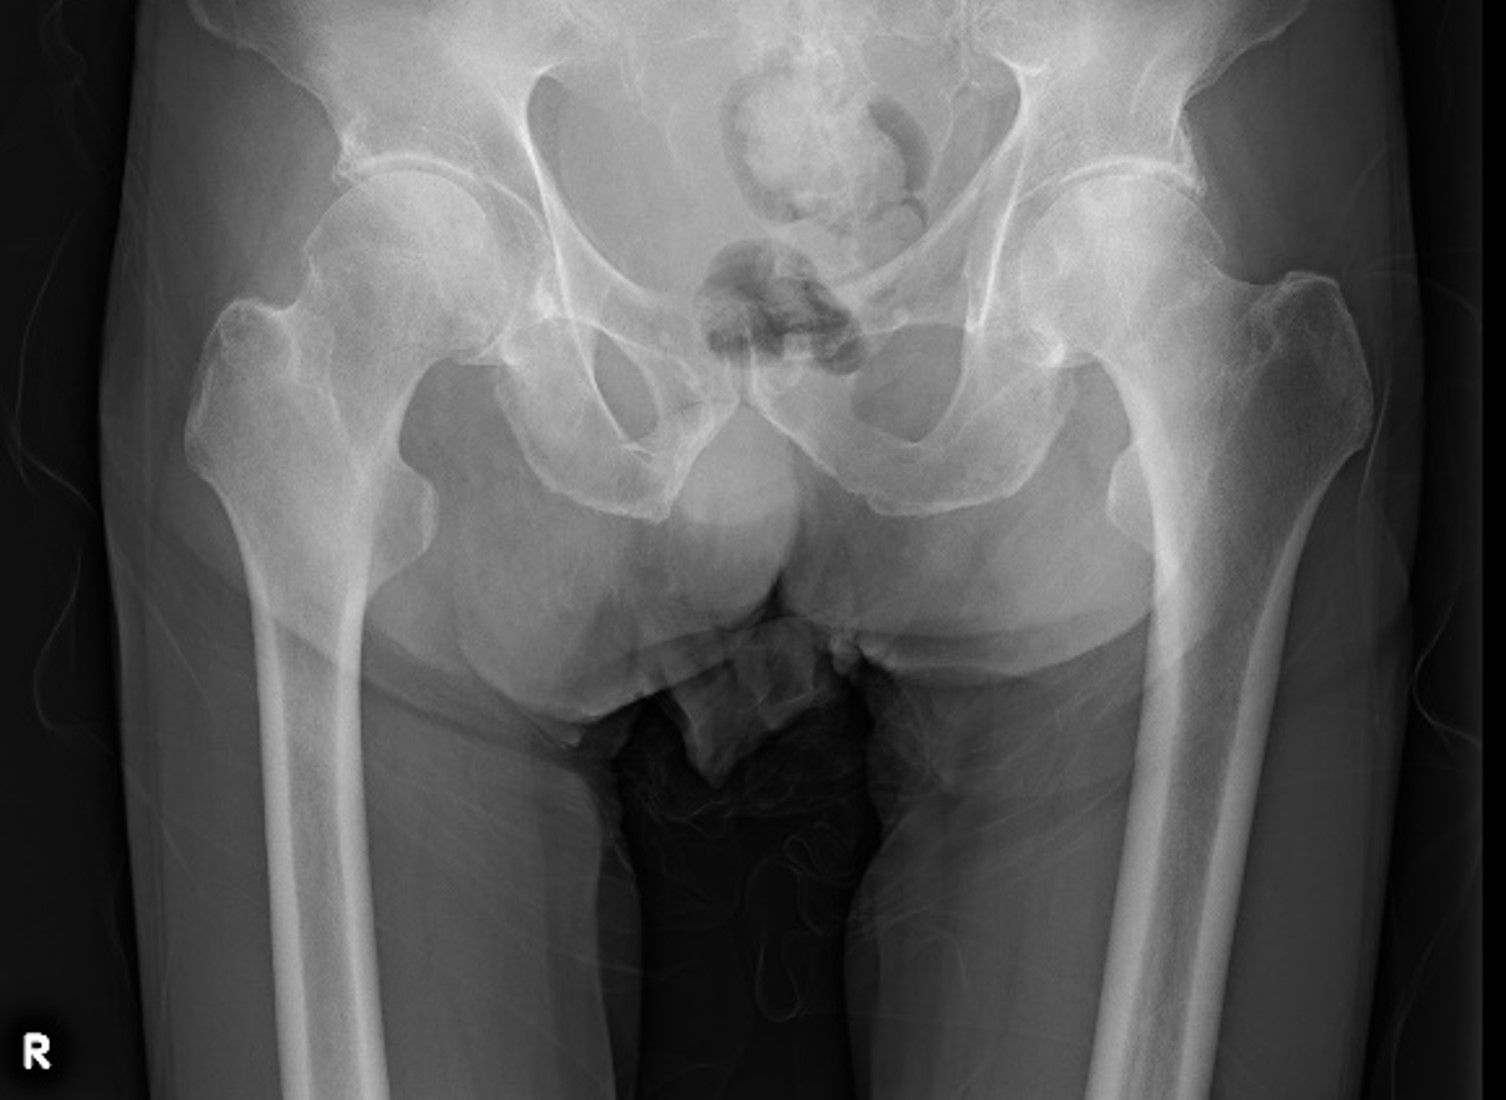

70歳代男性、検査前日に転倒しその後から右股関節痛があり歩行不能となった。図3、4にX線単純撮影を示すが、骨折を認めなかったためDE撮影を行った。

図5~7にコロナル2mmの各再構成画像を示す。

通常の骨条件でも骨折を指摘できなかったが、VNCa画像であるWater(HAP)で明瞭に骨髄浮腫を描出できた。CTに続き同日MRIも実施されたが、STIR(図8)でも同様な所見が描出されており整形外科医師にVNCa画像の有用性を理解していただけた。

RevolutionApexElite_Uonuma204.jpg図3 両股関節 正面像